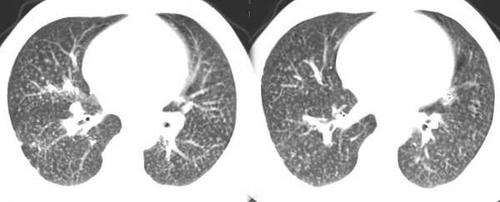

怀疑结核或者尘肺的!大家给点意见!

ct2940:胸部,尘肺乎.粟粒样肺结核乎.迷茫.

尘肺的影像表现及鉴别诊断